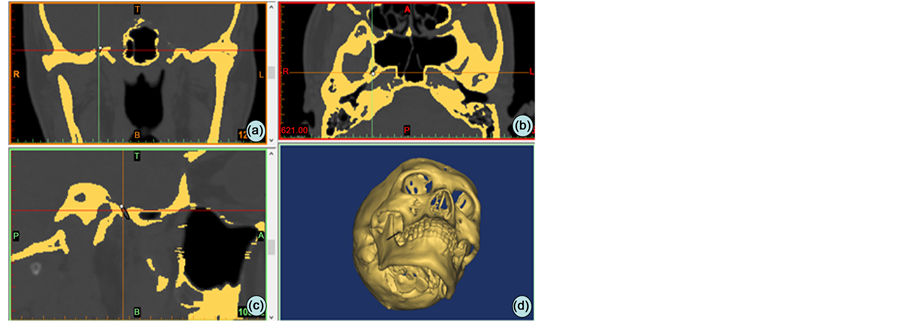

After image processing which contained thresh-holding and morphological operations, the model of encephalic and skin model were visualized (Figure 1), which were saved as Stereolithography (STL) files.

Figure 1. The DICOM data imported into MIMICS and mask of bone was threshold segmented ((a) coronal position; (b) axial position; (c) sagittal postion; (d) the reconstruction of bone).